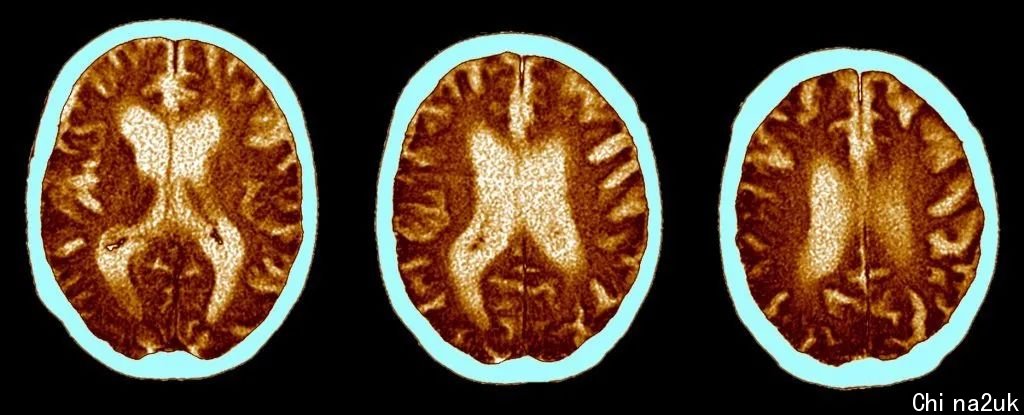

一项颁发在《电子临床医学》(eClinicalMedicine)杂志上,由剑桥大学和伦敦帝国理工学院联结钻研的讲演显示,愈来愈多的证据标明,那些承受过重大新冠病毒护理的人更可能遭遇耐久的认知问题。

这些认知问题与50至70岁之间因苍老酿成的影响类似,至关于失去10个智商点(IQ points)。

迷信家们剖析了2020年3月至7月期直接受新冠住院护理的46人的数据,这些人在承受重大新冠护理后均匀6个月,使用Cognitron平台进行了具体的计算机化认知测试。与对比对于组比拟,承受护理者精确度较低,反映时间较慢。

经过将患者与66,008名普通大众成员进行对比,钻研人员估量,认知才能丢失的水平均匀与50至70岁之间继续20年的苍老类似,这至关于失去10个智商点。

这与以前在感染新冠后视察到的大脑前额叶网络内的大脑葡萄糖损耗增加相统一,该网络担任留意力、繁杂问题的解决和任务记忆等功用。

且对那些需求使用呼吸机的患者来讲影响更显著。与此同时,钻研人员正告称,即便是那些没有住院的病人也可能有轻微脑损伤的迹象。

大脑扫描图象 | 图片来源ScienceAlert

以前在英国进行的一项钻研发现,大约七分之一的人在测试呈阳性的十二周后讲演有包罗认知难题的症状。即便是轻微病例也会致使继续的认知症状,但高达四分之三的住院病人讲演说六个月后仍有认知问题。

新冠会致使耐久的认知和心思安康问题,痊愈的病人在感染几个月后依然会泛起症状。讲演的症状包罗疲劳、脑雾、回想单词紊乱、睡眠障碍、焦虑,乃至创伤后应激障碍(PTSD)。

该钻研的资深作者、剑桥大学的David Menon传授说,认知障碍常见于各种神经零碎疾病,包罗痴呆症,乃至惯例老化,但新冠致使的认知问题与这些都不同。

在对一些病人的跟踪检测中显示,最晚在急性感染后的十个月,可以看到十分迟缓的改良。但其中一些人极可能永久不会彻底痊愈。